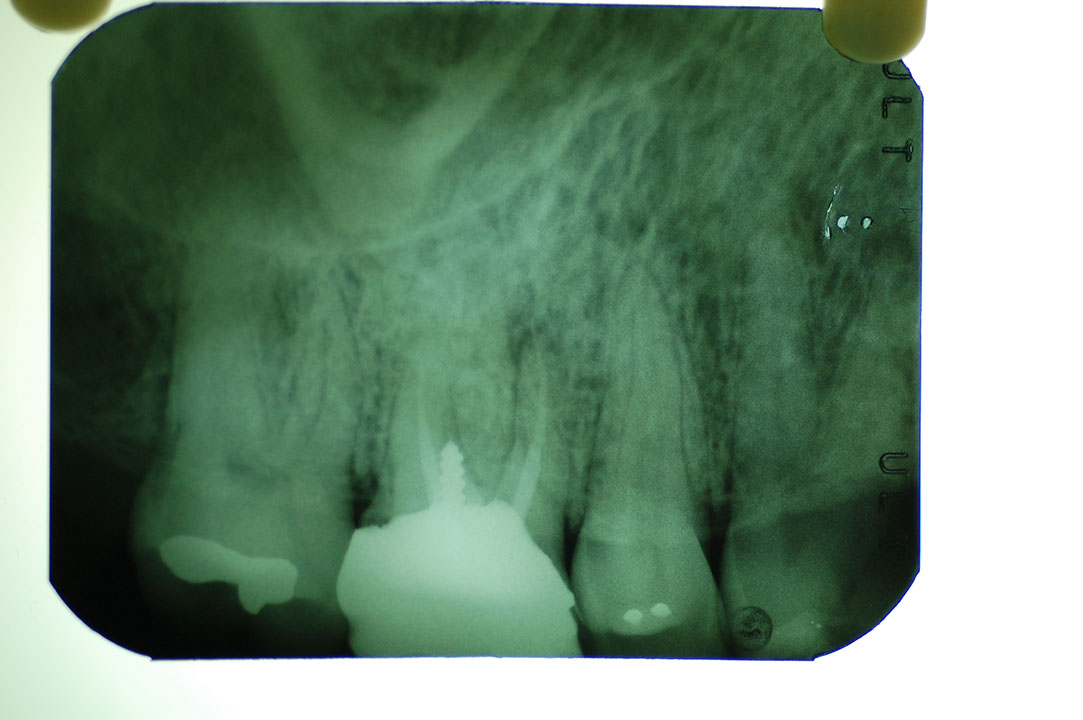

Post 5g7.JPG

光牙醫